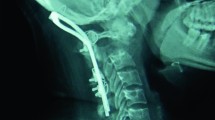

Spinal manipulation is effective for the treatment of many conditions, albeit not without possible complications. The incidence of subtle growth plate fractures following high-velocity techniques in children is surely under-appreciated because of the occult nature of these injuries.